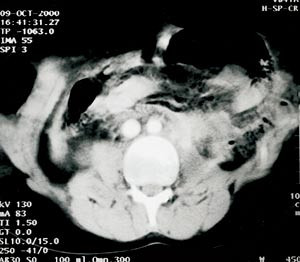

Pasient 2. En tidligere frisk åtte år gammel gutt ble innlagt i lokalsykehus etter fall fra tre meters høyde. Ved ankomst i sykehuset klaget han over abdominalsmerter. Ved klinisk undersøkelse fant man en palpabel hevelse i øvre venstre del av abdomen. CT viste en defekt i fremre bukvegg lateralt for rectusmuskulaturen med herniering av tynntarm (fig 2). Laparotomi ble utført gjennom en liten tverrincisjon over den palpable defekten. Brokkinnholdet viste seg å være spontant reponert. Det ble ikke påvist intraabdominal skade. Påfølgende dag ble den kliniske tilstanden betydelig forverret, og han utviklet peritonitt. Han ble overflyttet til Ullevål universitetssykehus. Ved relaparotomi fant man to liter gallefarget væske i buken og en perforasjon av jejunum like ved det Treitzske ligament. Postoperativt utviklet han akutt lungesvikt og ble respiratorbehandlet i en uke. Etter ekstubering hadde han en episode med transfusjonstrengende gastrointestinal blødning. Han ble overflyttet til lokalsykehus to uker etter skaden. Han ble operert for ileus etter tre uker, men kom seg raskt etter dette, og det er ikke påvist tegn til residivbrokk seks måneder etter skaden.

Begge våre pasienter ble undersøkt med CT, som tydelig viste bukveggsdefektene (fig 1, fig 2). CT er en god undersøkelsesmetode for å vurdere intraabdominal parenkymskade hos hemodynamisk stabile pasienter som har vært utsatt for stumpe abdominaltraumer, og er den beste radiologiske undersøkelse for å påvise traumatiske bukveggsbrokk (7). CT-undersøkelse gir en nøyaktig avgrensning av defekten og kan identifisere brokkinholdet. Det er her viktig å minne om at kort tid etter skaden kan en hulorganskade være vanskelig å diagnostisere så vel klinisk som ved CT.